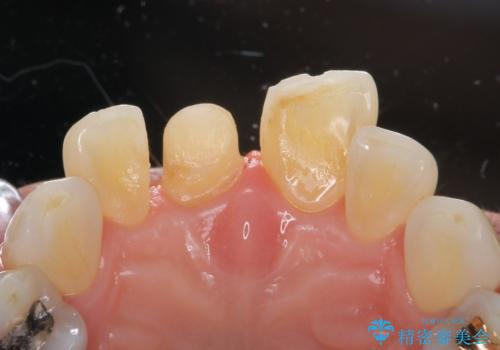

- 転んで前歯が折れたとのことで来院されました。

検査の結果、歯は大きく折れておらず、骨の中に埋め込まれていた状態であったため、部分矯正で歯を引っ張り出していきます。

ぶつけて埋まってしまった歯は、場合によって矯正治療で引っ張り出すことで保存することができます。

今回は歯の神経が死んでしまっていたため、根管治療後に被せ物を装着して見た目の綺麗さを回復しました。